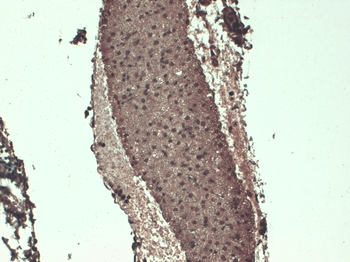

IF analysis of mouse ovary tissue using anti-NIS (2.5 ug/ml)

IHC-P image of mouse ovary tissue using NIS antibody (2.5 ug/ml)

IF image of mouse ovary tissue using NIS antibody (2.5 ug/ml)